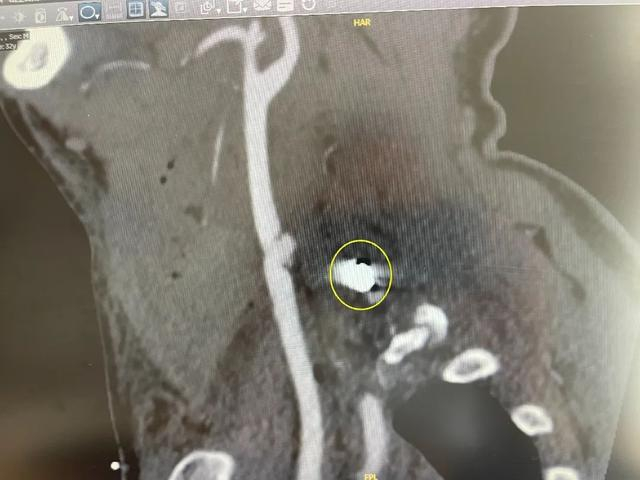

陈先生被快速送到温岭当地医院。CT检查发现,他的颈动脉破裂,正在往外冒血,大部分血液滞留在颈部,脖子被撑得粗了一圈

颈动脉破损处形成的假性动脉瘤

在DSA(数字减影血管造影)检查下,一颗直径约8毫米的异物在影像中显露高密度白色身形,刚好卡在颈椎间隙,没有伤到颈椎。医生们松了一口气,这也意味着,一切都在他们的掌握中。

卡在颈椎间隙的异物